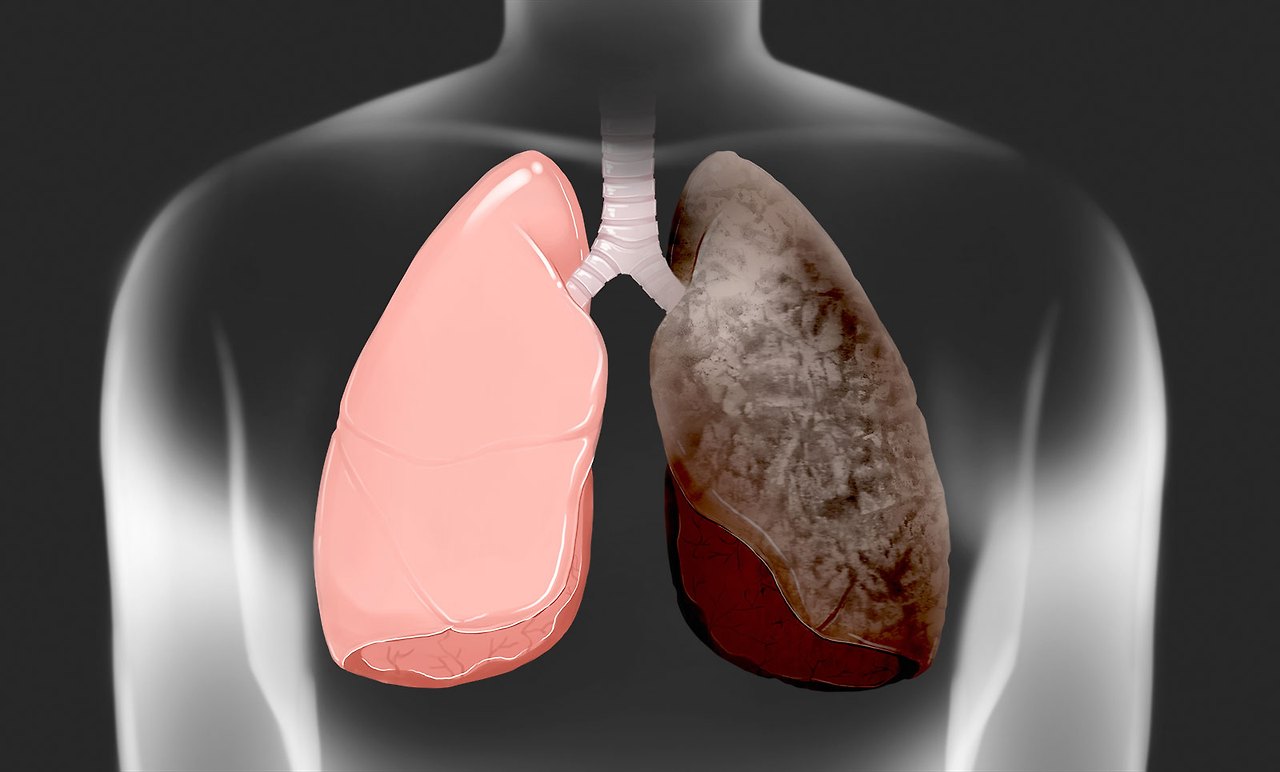

폐암은 조기에 발견하지 않으면 치료가 어려워 생존율이 낮은 암 중 하나입니다. 그러나 초기 증상을 인지하고 검사를 통해 조기에 발견하면 치료 가능성이 높아집니다. 폐암 초기 증상과 검사 방법을 알아두어 조기 진단의 중요성을 강조하고, 건강을 지키는 방법을 소개해드리겠습니다.

폐암은 조기에 발견할수록 생존율이 높아지기 때문에, 초기 증상을 인지하고 정기 검진을 통해 조기에 발견하는 것이 중요합니다. 특히, 흡연자나 폐암 가족력이 있는 사람은 정기적인 검사를 통해 폐암 위험을 미리 확인하고 예방하는 것이 필요합니다.

폐암은 초기 증상이 뚜렷하지 않아 조기 발견이 어려운 경우가 많지만, 정기 검진과 초기 증상에 대한 인식을 통해 예방할 수 있습니다. 폐암의 위험을 줄이기 위해서는 금연, 건강한 생활습관 유지, 정기적인 검진을 통해 건강을 지키는 것이 중요합니다.